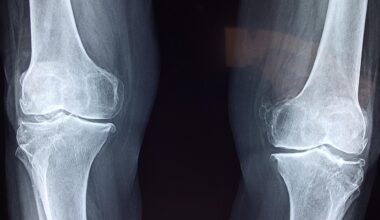

Injury recovery, particularly in relation to neuromuscular re-education therapy, relies heavily on effective assessments. These assessments guide clinicians to optimize treatment plans, resulting in better outcomes for patients. They enable professionals to evaluate the functionality of muscles and neural pathways effectively. Numerous assessment tools exist, each serving specific purposes. For instance, subjective measures often include patient-reported outcomes that gauge pain levels, functional capacities, and overall well-being. Objective measures encompass physical performance tasks and standardized tests that quantify progress. Among these tools, clinicians frequently utilize scales and questionnaires that provide insight into patients’ experiences. Additionally, diagnostic imaging techniques, such as ultrasound and MRI, may complement functional assessments. These imaging modalities help visualize anatomical structures and identify any abnormalities. Moreover, the utilization of technology such as wearable sensors further assists in tracking movement patterns and muscle activation. Regular outcome assessments not only inform therapeutic adjustments but also bolster patient motivation as they witness improvements. Ensuring that these assessments are regular and accurate is crucial to maximizing rehabilitation efficacy. Overall, these evaluation techniques form the backbone of successful neuromuscular rehabilitation practices.